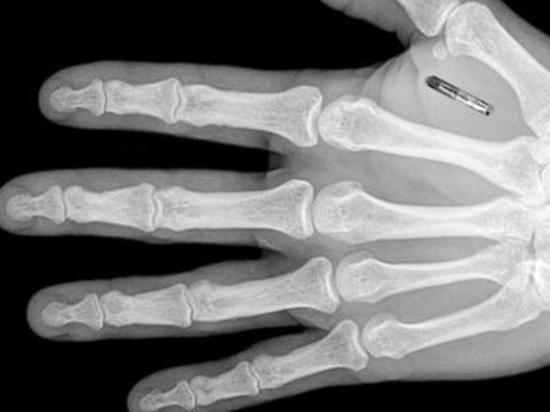

Процедурата по имплантиране на чипа е подобна на тази при поставянето на пиърсинг, като първо се нанася дезинфектант на горната страна на китката в сектора между палеца и показалеца, след което чипът се инжектира със спринцовка. Келсинг каза пред Франс прес, че по време на процедурата е почувствала само леко щипане.

Имплантирането на чипове е организирано от шведска биохакерска група. Освен че могат да бъдат лесно имплантирани, чиповете могат да бъдат и лесно премахнати, уверяват организаторите. Животът им е над 10 години, а цената – 3000 долара.